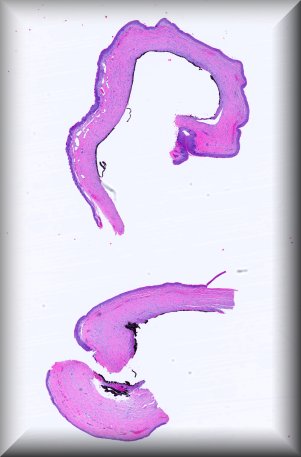

Daniela Süsskind (Tuebingen): Rapidly growing tumor of the conjunctiva in an 86 years old woman presenting as a masquerade syndrome with signs of intraocular inflammation. |